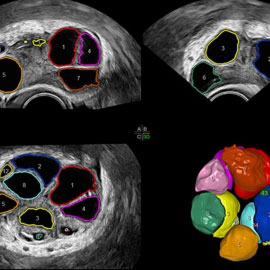

والتي يتم فيها تطبيق برامج تحريض الإباضة لمختلف تقنيات الإخصاب المساعد طبياً مع إجراء رصد للجريبات المبيضية ومراقبة تطورها، إضافة إلى دراسة بطانة الرحم والجريان الدموي ضمنها باستخدام الإيكو دوبلر الملون. وتم حديثا إضافة دراسة مشعر التعشيش أو الانغراس مع دراسة دوبلر الشريان الرحمي.